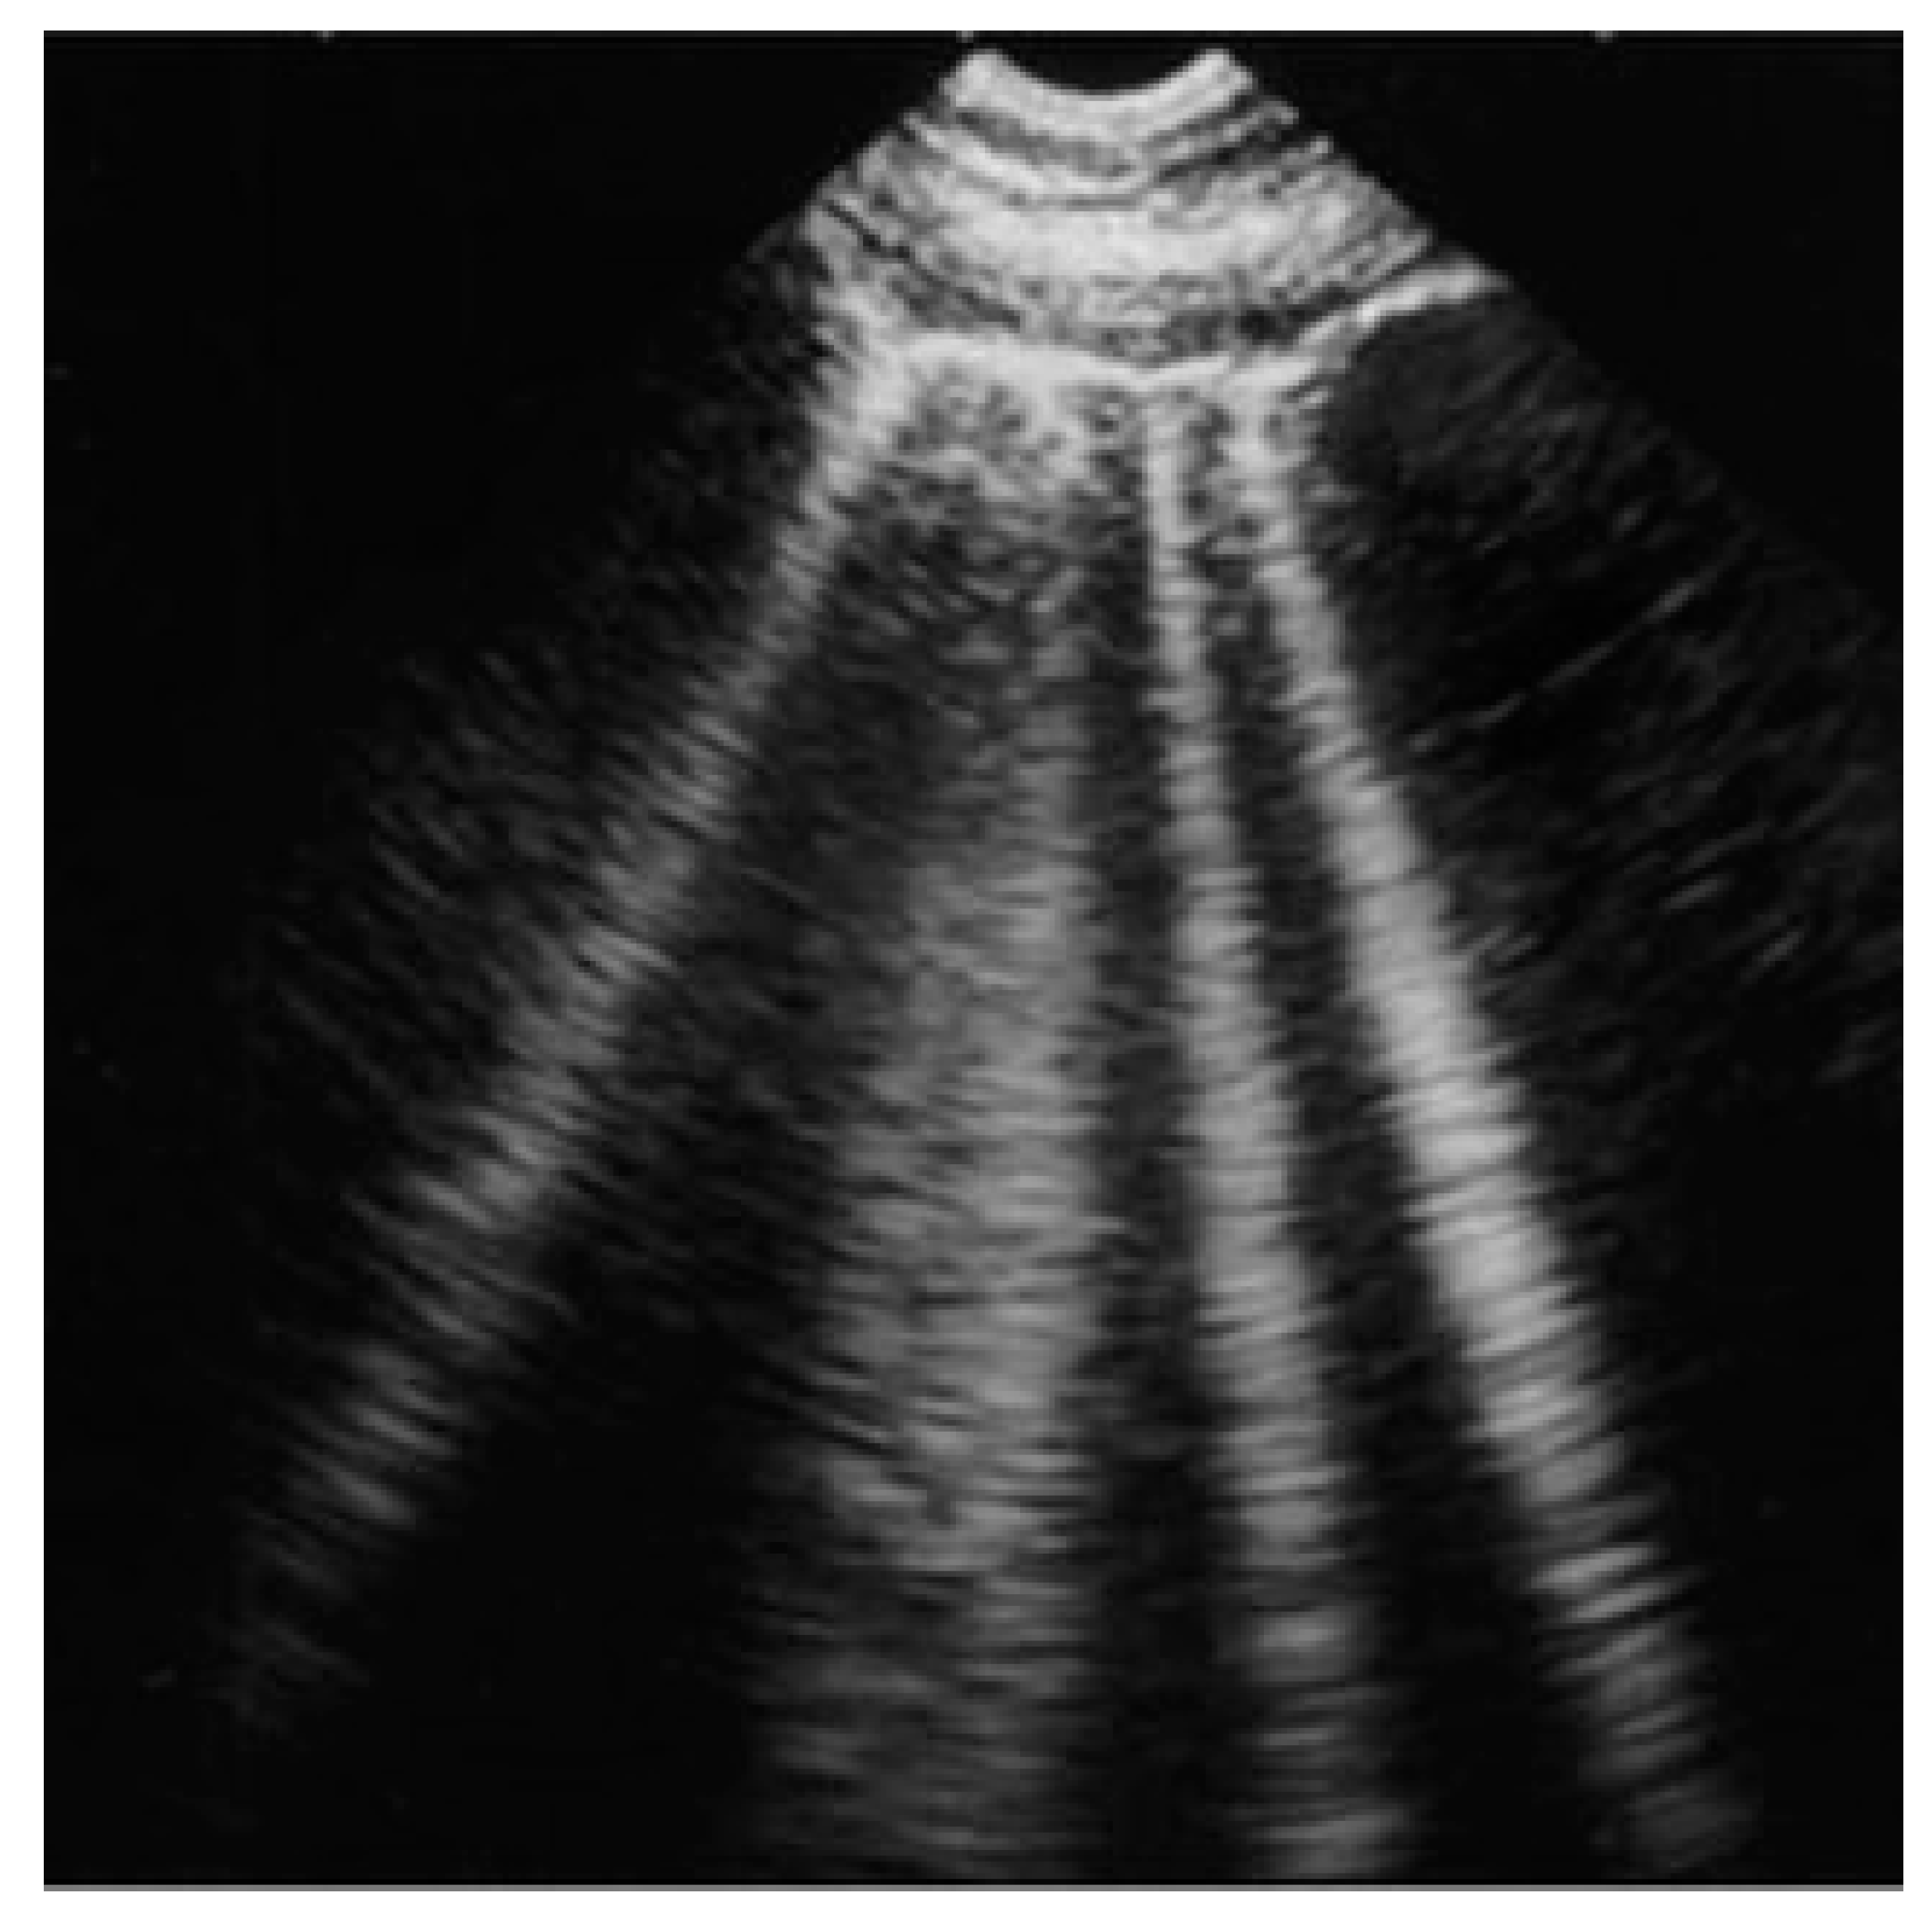

| Acute and chronic HF | Hyperechoic vertical lines extend from the pleural line (which is not thickened) and radiate towards the edge of the echocardiographic field. | ![]() |